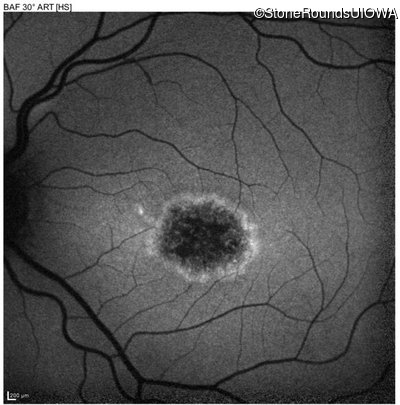

Blue Autofluorescence - Right - 20/160 +2 sc

Exemplar